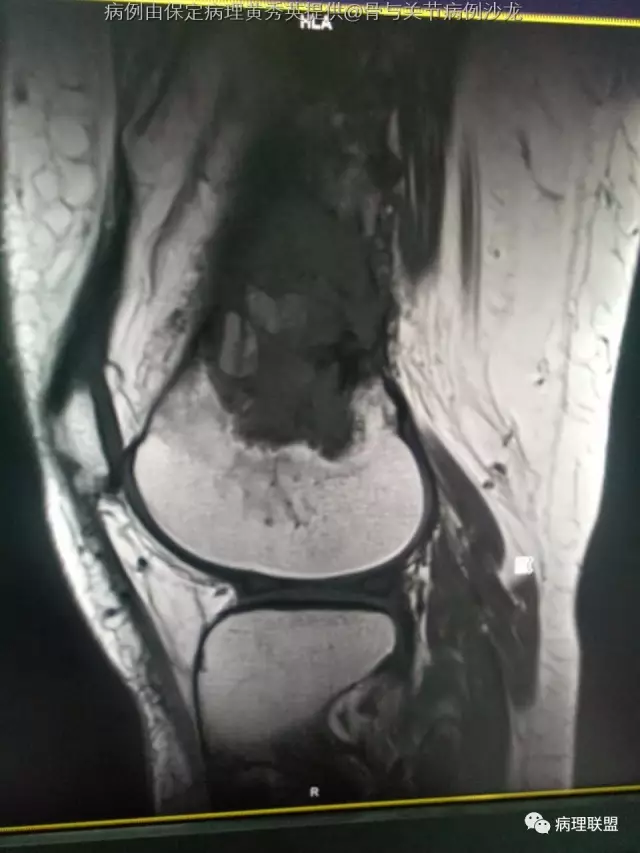

女67岁,股骨下端肿物约6cm,(病例由保定病理黄秀英提供,致谢!)